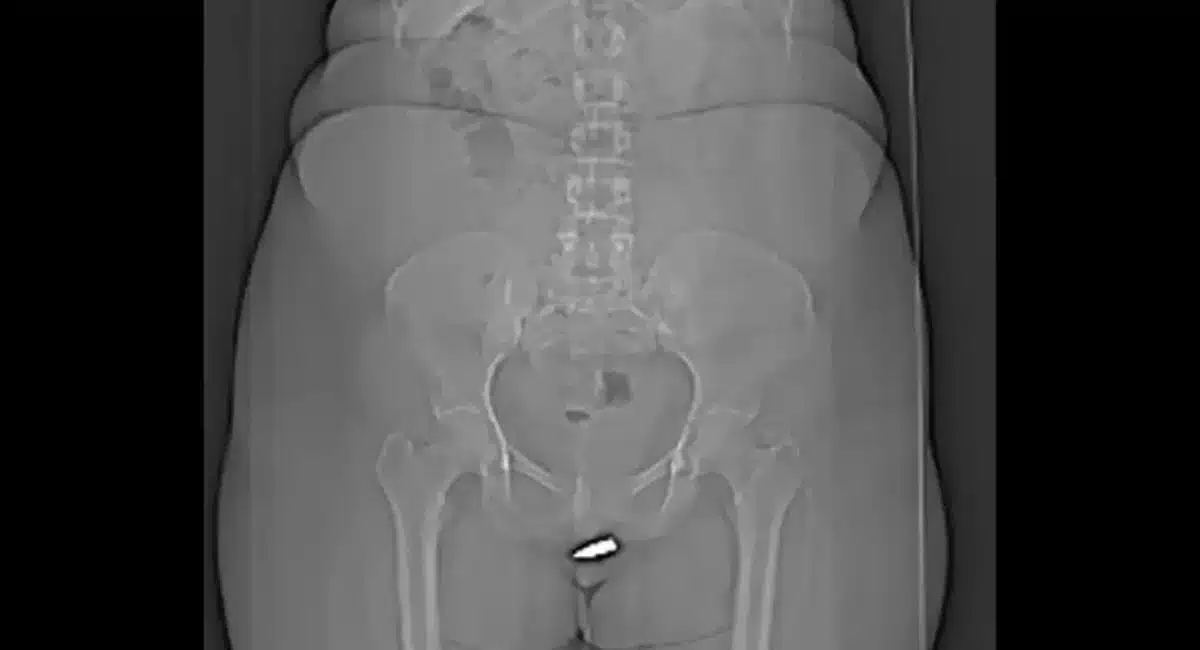

దీంతో వెంటనే కుటుంబ సభ్యులు చుట్టుపక్కల ప్రాంతాల ప్రజలు స్థానికులు సదరు యువతని వెంటనే ఎర్డోగన్ ఆసుపత్రికి తరలించారు. వైద్యులు ఎక్స్ రే తీసి చూడగా ప్రైవేట్ పార్ట్ లో రెండు సెంటీమీటర్ల బులెట్ గుర్తించడం జరిగింది. ఈ కేసుకు సంబంధించిన వివరాలను ఇంటర్నేషనల్ జర్నల్ ఆఫ్ సర్జరీ కేస్ రిపోర్ట్స్ లో ప్రచురించడం జరిగింది. తక్కువ వేగంతో బుల్లెట్..

జననేంద్రియాల్లోకి వెళ్ళటంతో.. సదరు యువతీ ప్రాణానికి ఎటువంటి ప్రమాదం జరగలేదని లేకపోతే… ఆమె తీవ్ర గాయానికి గురయ్యే అవకాశం ఉండేదని తెలియజేయడం జరిగింది. శాస్త్ర చికిత్స చేసి సుమారు నెలరోజుల పాటు వైద్యుల పర్యవేక్షణలో సదరు యువతని ఉంచారు. తర్వాత డిశ్చార్జ్ చేయడం జరిగింది. ప్రస్తుత ఆమె ప్రాణానికి ఎటువంటి ప్రమాదం లేదని వైద్యులు నిర్ధారించుకున్నాక.. ఇంటికి పంపించడం జరిగింది.